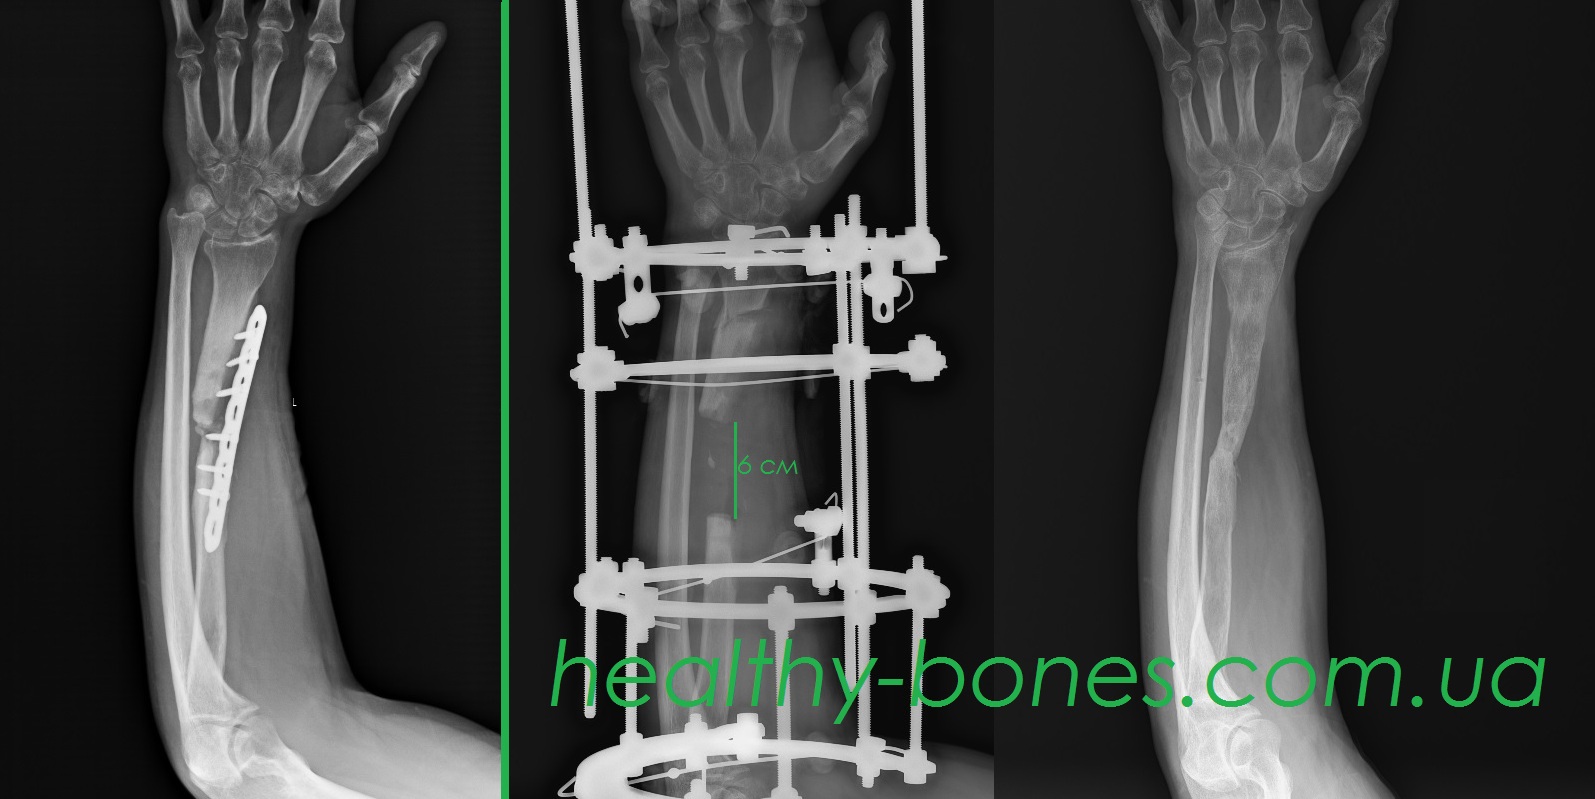

Іван, 29 років